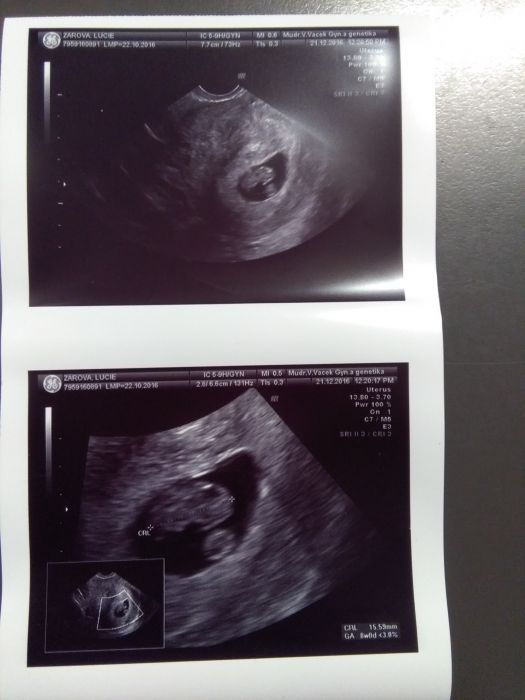

Kontrola v poradku, dalsi 11.1 :-) videla i slysela jsem srdicko a pry je vse ok, mam nove foto, tak to bude pod stromecek pro moje kluky :-) jsem zvedava jak budou reagovat :-) jsem 8+4, podle ultrazvuku 8+0.